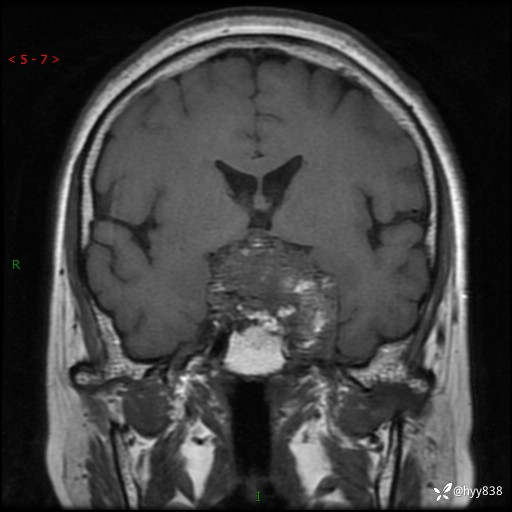

增强 COR +SAG